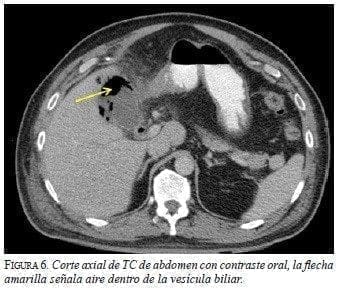

La TC informó derrame pleural e imagen sugestiva de proceso neumónico basal en el hemitórax derecho, y en el abdomen aire dentro y en la pared de la vesícula (figura 6), con solución de continuidad y colección perivesicular con contenido de gas (figura 7).

![]() |

Figura 7.

Corte axial de TC de abdomen con contraste oral, la flecha amarilla señala aire dentro de la vesícula biliar, las flechas blancas muestran aire en su interior y la flecha negra muestra colección perivesicular con aire en su interior, correspondiente a perforación vesicular.